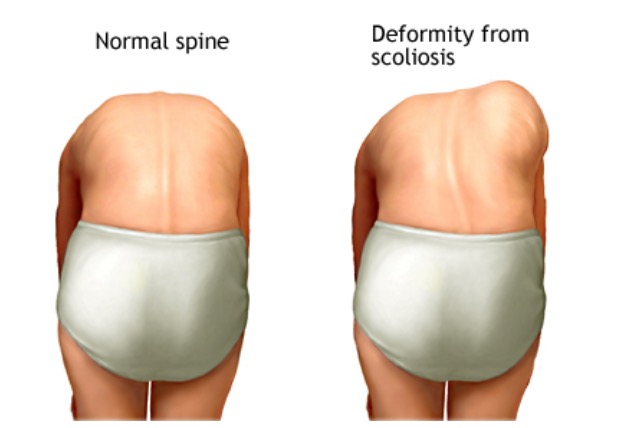

脊柱侧弯是指脊柱垂直方向的偏离。虽然有许多关于脊柱侧弯治疗方法的研究,但关于其病因和病理的研究数量有限。

脊柱侧弯最常影响女孩。有些人的脊椎更容易弯曲。在生长高峰期,弯曲通常会变得更糟,往往呈字母S或C型。

・臀部或肩膀不平(一个肩膀可能比另一个高);

・脊椎更多地向一侧弯曲

弯腰实验,你可以在家里完成筛查!

必要时进行体格检查。你将被要求做弯腰实验。这使你的脊椎更容易看到。但在脊柱侧凸的早期可能很难看到变化,必须借助X光片等其他影像学检查。